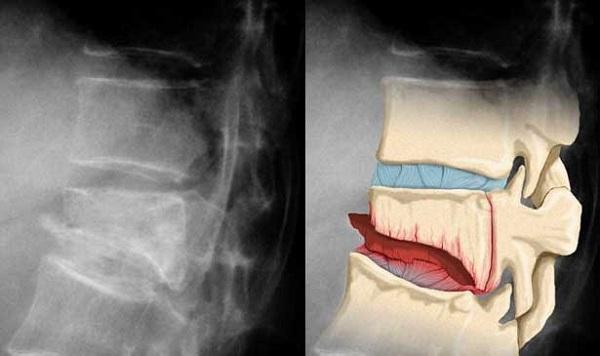

Компрессия и декомпрессия – два противоположных физических явления. Первое представляет собой сдавливание физического тела, другое – растяжение. Оба этих понятия при чрезмерном воздействии на организм нарушают целостность структур объекта. Смотрите фото.

Сталкивая с проблемой, человек задается вопросом, чем отличается декомпрессионный перелом позвоночника от компрессионного. Разница состоит в том, что в первом варианте позвоночник подвергается растяжению, в результате чего повреждаются мягкие ткани и спинной мозг.

Во второй ситуации возникает одновременное сжатие и сгибание одного или нескольких позвонков, в результате утрачивают свою целостность не только мягкие ткани, но и костные структуры.

Помимо характерного болевого синдрома и утраты способности самостоятельного передвижения, снимки рентгенографии свидетельствуют о наличии травмы.

Рентген выполняется в боковой и фронтальной проекции, после чего хирург может оценить степень разрушения тела одного или нескольких позвонков. Для определения степени повреждения мягких тканей назначается МРТ и КТ.